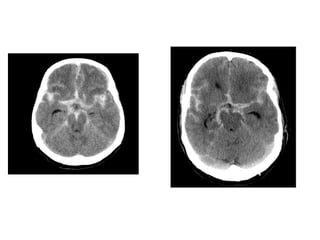

• Neuroimaging:

– CT and MRI methods appear to be equally sensitive.

– CT Scan: Intracranial Hemorrhages.

– MRI: Useful for posterior fossa and temporal lobe.

Investigations: • CBC- Whensystemic or intracranial infection suspected. • Neuroimaging: – CT and MRI methods appear to be equally sensitive. – CT Scan: Intracranial Hemorrhages. – MRI: Useful for posterior fossa and temporal lobe. • Lumbar Puncture: CSF fluid analysis.